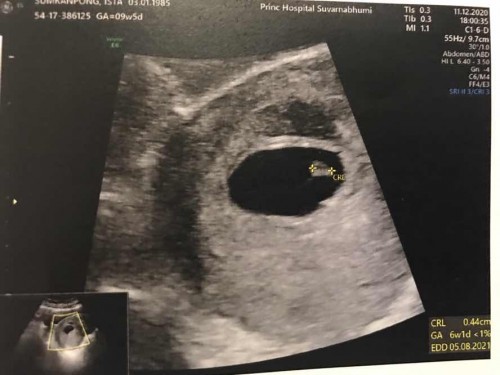

9สัปดาห์แล้วแต่ยังเป็นแค่ถุงไข่แดง ควรรอต่อหรือพอแค่นี้ดีคะ มีใครที่รอนานประมาณนี้บ้างไหมคะ

หมอบอกเห็นแค่ถุงไข่ และขอบของถุงตั้งครรภ์ไม่ค่อยเรียบ ให้เผื่อใจด้วย

ใบซาว6wเองค่ะแม่ รออีกหน่อยนะคะ